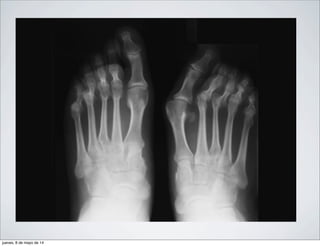

PIE Y TOBILLO

HALLUXVALGUS

DEDO EN

MARTILLO